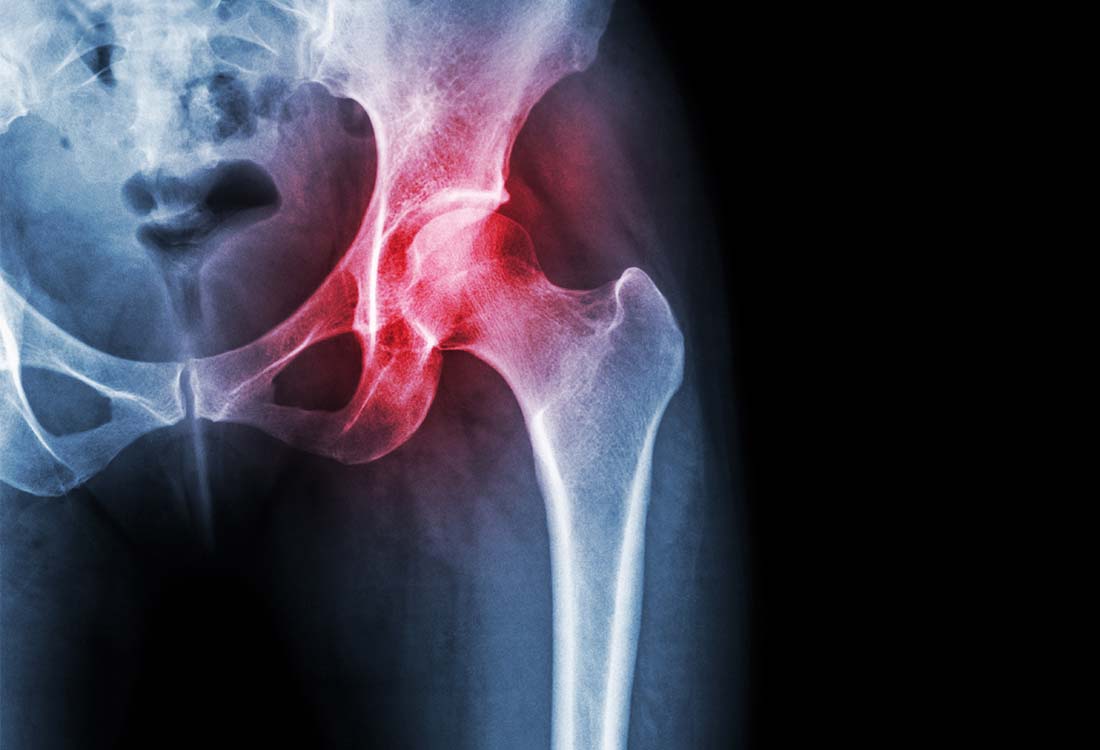

Anschließend wird in der Regel ein Röntgenbild des betroffenen Gelenks angefertigt. Da Knorpelgewebe im Röntgenbild nicht sichtbar ist, werden nur die gelenkbildenden Knochenanteile dargestellt. Eine Verschmälerung des Gelenkspaltes, die auf den Rückgang des Knorpels hinweist, ist im Röntgenbild gut erkennbar. Außerdem können Knochenanbauten (Osteophyten) und eine Verdichtung der gelenkbildenden Knochenstrukturen (Sklerose) im Röntgenbild gesehen werden.

Röntgenbild einer Hüfte mit Arthrose – entzündete und abgenutzte Gelenkflächen.